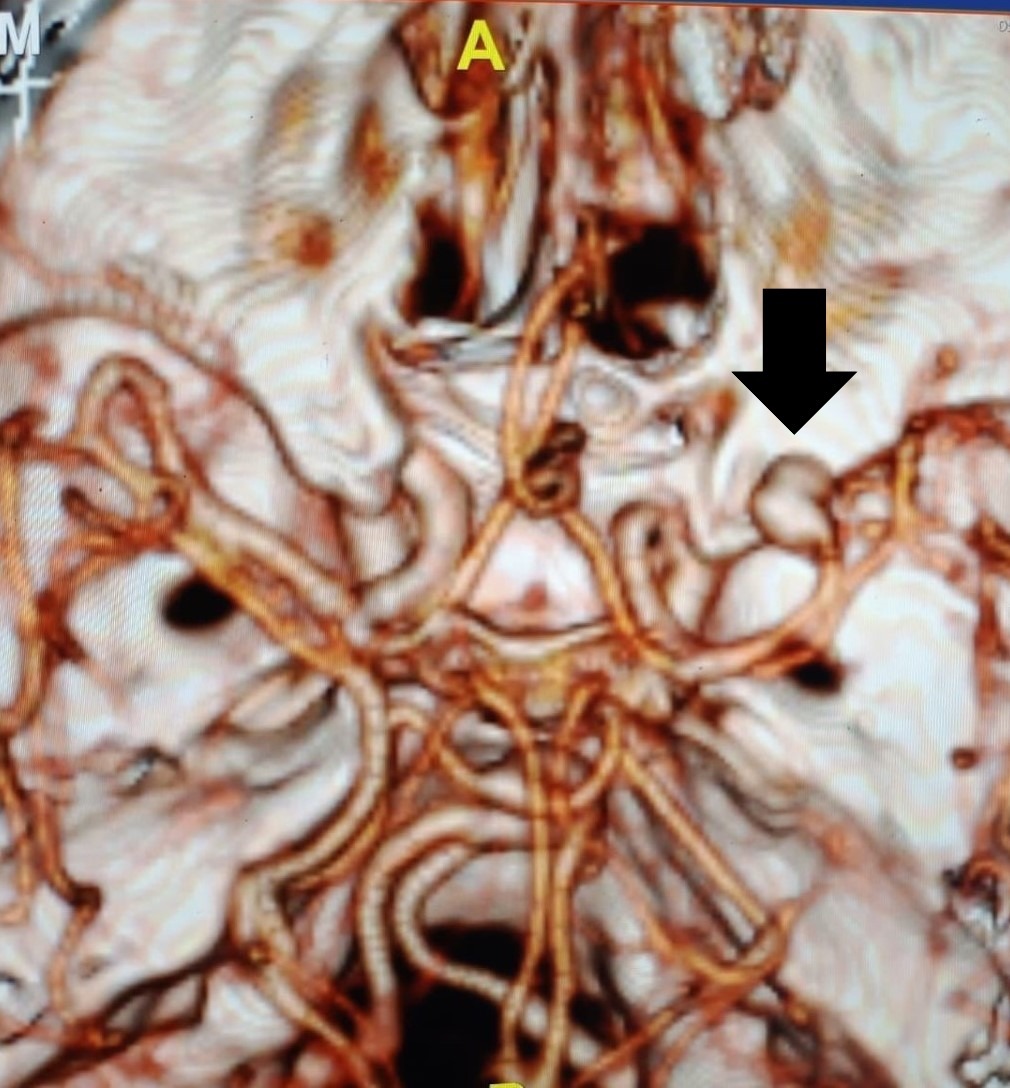

The patient underwent right pterional craniotomy under general anaesthesia. Standard microsurgical dissection along the sylvian fissure was performed. The M1 segment of the MCA was identified and followed distally. The anomalous orbitofrontal branch was identified arising from the superior aspect of the M1 segment. The saccular aneurysm arose from this branching point and measured approximately 7 mm in maximum diameter. The aneurysm neck was carefully dissected free from surrounding arachnoid adhesions and perforating vessels. Two titanium clips were applied across the aneurysm neck, achieving complete obliteration of the aneurysm while preserving the parent orbitofrontal artery and adjacent MCA branches [Figure 4]. Intraoperative indocyanine green (ICG) video angiography confirmed complete aneurysm occlusion with preserved flow in all adjacent vessels. The orbitofrontal artery was successfully preserved. The pterional exposure was adequate to visualize parent vessel anatomy and ensure optimal clip positioning. Hemostasis was achieved, and the craniotomy was closed in standard fashion.

Post-operative NCCT brain and CTA demonstrated complete aneurysm obliteration without residual filling or parent vessel compromise [Figure 5]. The patient was discharged on post-operative day 7 without neurological deficits. Clinical examination remained unremarkable on discharge, with intact higher mental functions. At weekly and subsequent monthly follow-up appointments, he remained neurologically intact without recurrent symptoms, vasospasm related complications and there was no evidence of delayed cerebral ischemia, hydrocephalus, or clip migration. Neuropsychological assessment revealed no cognitive deficits or frontal lobe dysfunction. Higher mental functions remained completely intact. At three-month follow-up, the patient had resumed occupational activities without restrictions.